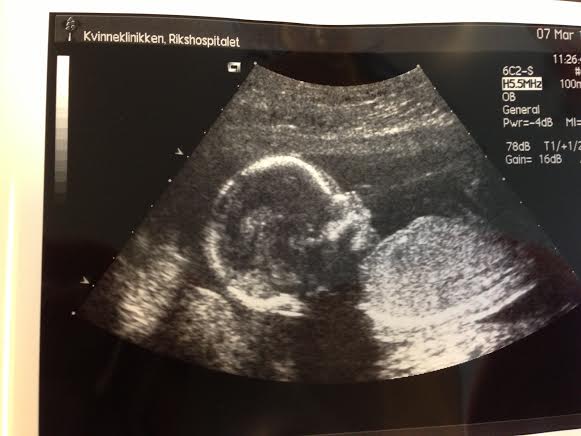

Ikke noe superbra bilde, men du har selvsagt helt rett hvis du syns denne ungen ser litt ekstra spesielt supersøt ut. Det er han fortsatt 🙂